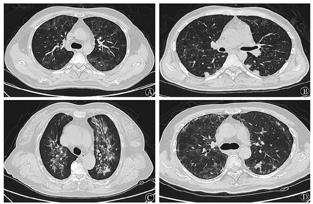

采用飞利浦Ingenuity 64排128层螺旋CT机,管电压120 kV,管电流200 mA,准直64×0.625 mm,矩阵512×512,扫描范围自肺尖至肺底,于深吸气末屏气扫描,层厚5 mm,间隔5 mm。肺窗窗宽1 000 Hu,窗位-700 Hu;纵隔窗窗宽400 Hu,窗位45 Hu。根据初始CT肺窗表现对所有患者进行归纳分型,共分为4种类型:①磨玻璃型:表现为两肺内中带弥漫分布的磨玻璃影,胸膜下区不受累(图1A);②结节型:表现为肺内多发小结节影,包括间质结节、小叶中心结节及树芽征(图1B);③纤维化型:表现为肺内多发索条影、支气管轻度牵拉扩张,部分可伴有肺实变(图1C);④混合型:表现为多种影像征象并存,包括磨玻璃影、小结节及索条影共存(图1D)。

46例患者初始胸部CT检查均可见异常,磨玻璃型26例(56.5%)、结节型10例(21.7%)、纤维化型4例(8.7%)、混合型6例(13.0%)。确诊、PB-mNGS诊断和BALF-mNGS诊断患者的CT类型分布见表2,差异无统计学意义(χ2=11.039,P=0.087)。确诊患者和PB-mNGS诊断患者均以磨玻璃型表现为主,分别占63.6%、73.7%,而BALF-mNGS诊断组CT表现以结节型居多,占37.5%,磨玻璃型占31.3%。19例allo-HSCT受者和27例非移植患者在CT类型差异亦无统计学意义(χ2=5.847,P=0.119),均以磨玻璃型表现为主,分别占57.9%、55.6%(表2)。不同CT类型患者的外周血淋巴细胞减少率、G试验阳性率和LDH升高率的差异均无统计学意义(表2)。

免疫抑制宿主合并PJP其CT多表现为肺门周围分布的磨玻璃影、胸膜下区一般不受累[8],少数可表现为单发或多发结节、树芽征、实变、空洞、纵隔淋巴结增大和胸腔积液等[1, 9,10,11,12]。本组结果显示,血液病患者合并PJP最常见(56.5%)的CT表现为两肺弥漫多发磨玻璃影,与文献报道相符。但与既往研究不同的是,本组病例中21.7%的患者CT为表现为多发结节,这部分患者多数(60%)经BALF-mNGS检测获得病原学结果。此外另有13.0%和8.7%的患者CT表现为混合型和纤维化型,12例(26.1%)患者伴有胸腔积液。